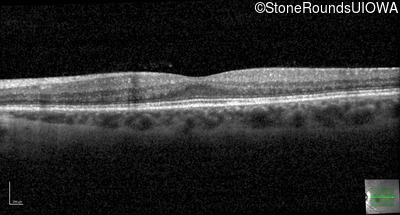

Optical Coherence Tomography - Right - 20/25 -1 sc

Exemplar / OCT Stack

OCT Stack